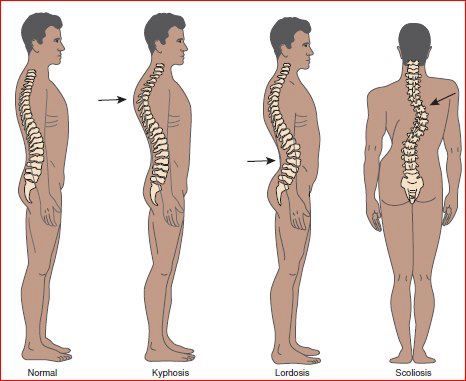

Poor Posture

Maintaining an incorrect posture while sitting or standing, prolonged use of mobile phones or laptop, can cause strain in the neck muscles and lead to pain.